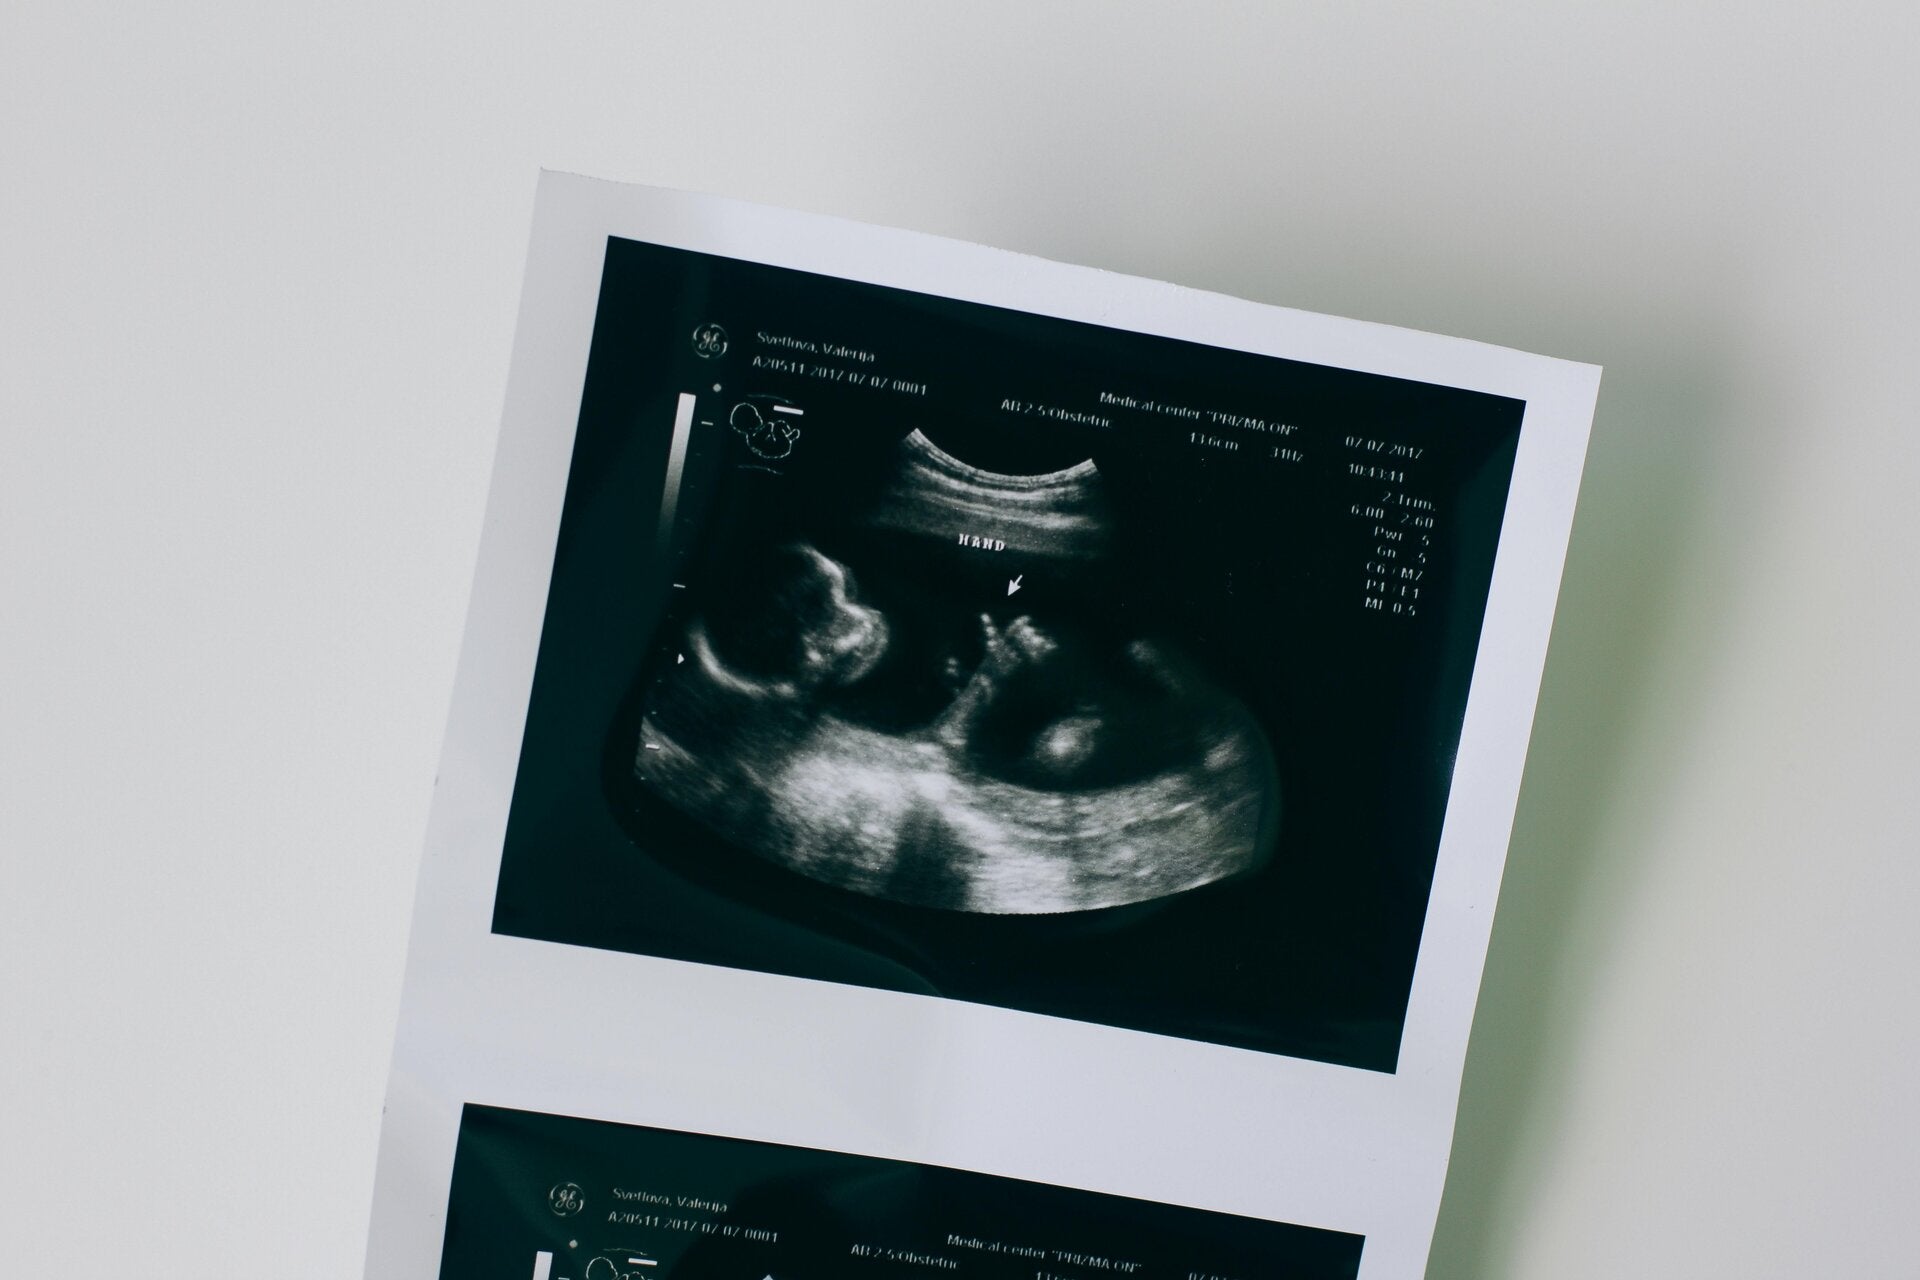

Wachstumskontrollen mittels Ultraschall sind wichtige Untersuchungen, um das Wachstum und die Entwicklung des Babys im Mutterleib zu überwachen. Diese regelmäßigen Untersuchungen ermöglichen es, frühzeitig eventuelle Probleme zu erkennen und entsprechend zu handeln.

Neben den regulären Ultraschalluntersuchungen bieten wir auch zusätzliche Ultraschalle an. Diese speziellen Untersuchungen können je nach Bedarf durchgeführt werden und liefern detaillierte Einblicke in die Gesundheit des Babys und der Mutter.